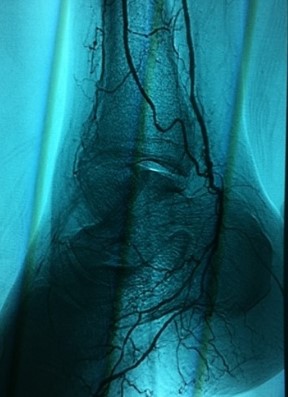

Image

673 Restoration

Restoration of blood flow to foot

of patient.